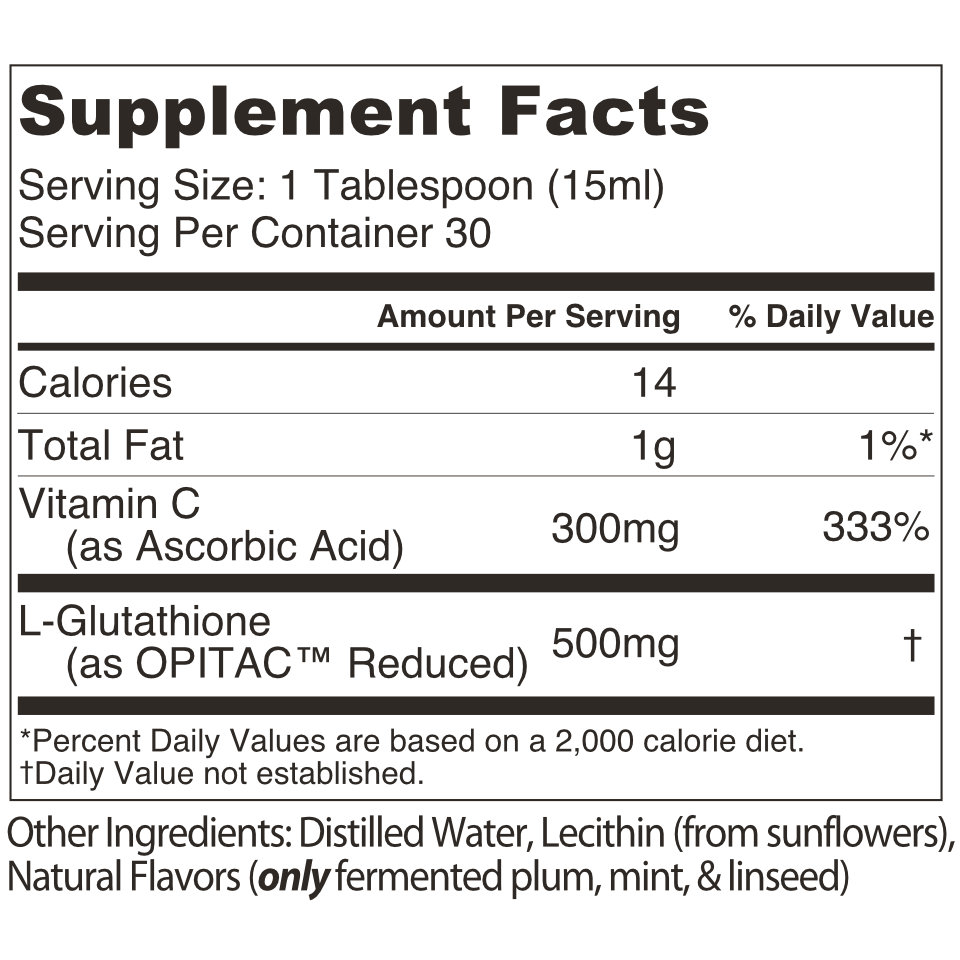

Supplement Facts & Ingredients

Serving Size: 1 Tablespoon (~15 ml)

Serving Per Container: 30

Amount Per Serving

- L-Glutathione (OPITAC®) Reduced: 500mg

- Vitamin C (as L-Ascorbic Acid): 300mg

Other Ingredients: Distilled Water, Lecithin (from sunflowers), Natural Flavors (only fermented plum, mint, & linseed)

Vegan Food. Free of... Gluten, Soy, Alcohol, Sugar, or Dairy.

No GMO, MSG, or other mystery ingredients. 100% Sourced from USA, Japan, and Europe.